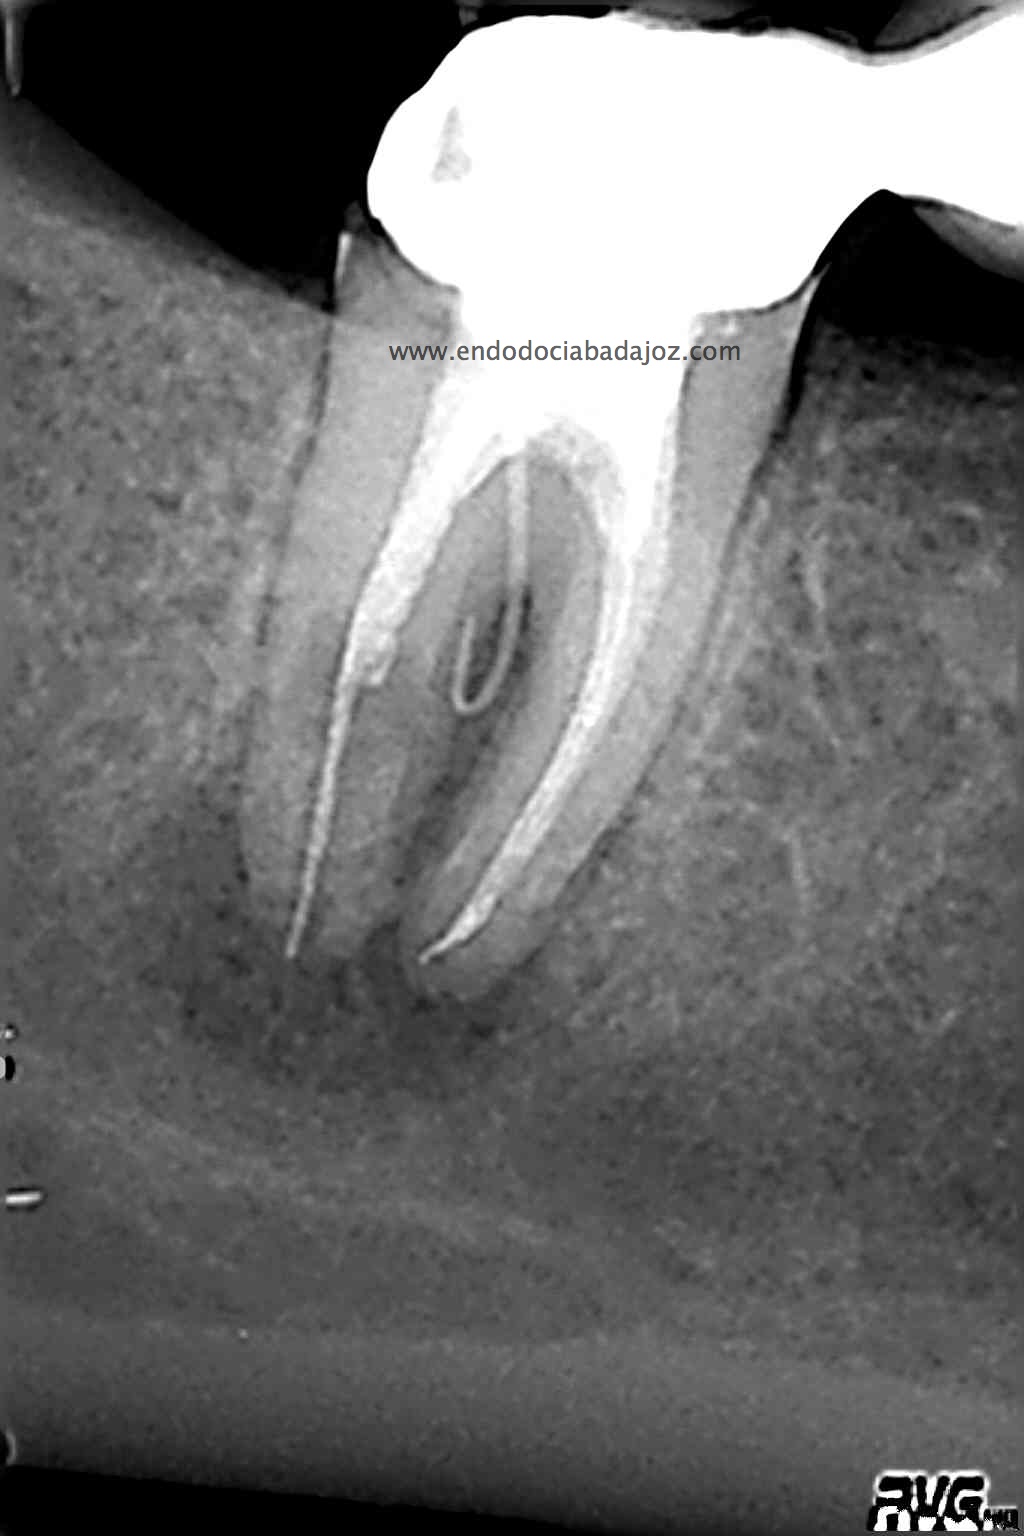

Acude a nuestra clínica una paciente que llamamos a revisión después de realizarle un retratamiento endodóntico de la pieza 4.7 hace unos meses. Si recordamos el día que llegó, no se nos presentaba muy bien el caso, y como otros muchos casos, intentamos retratarlo, pues pensamos que podríamos manejarlo.

Este caso lo resolveríamos en varias sesiones, después del manejo de los conductos mesiales, con una preparación biomecánica terminando en una conicidad del 6% y un diámetro apical de 30 en conductos mesiales.

Con ayuda del microscopio, pudimos confirmar que se trataba de una reabsorción interna en el tercio medio y una reabsorción radicular del conducto distal.

Bueno, pues el conducto distal se obturó en su tercio apical y medio con M.TA.

Hemos llamado a revisión a la paciente en varias ocasiones ( 6 meses y 9 meses)

(revision a los 6 meses) (revisión a los 9 meses)

Como podemos observar, la lesión periapical ha regenarado: